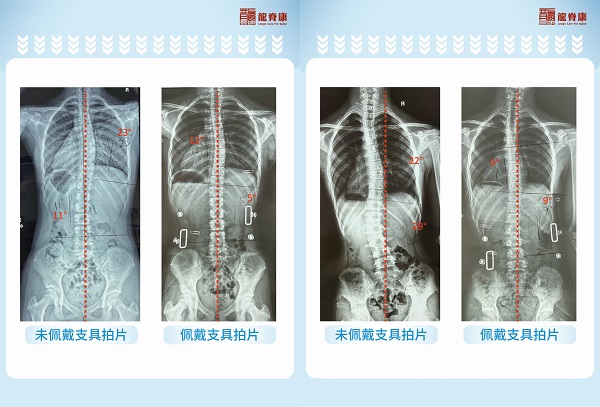

龙脊康自2012年开业以来,用13年的坚守,书写了一段辉煌的篇章:100,000+人次 脊柱侧弯及体态不良患者的诊治、3,000+副 定制支具、64% 的支具下平均矫正率、针对脊柱侧弯和青少年体态不良常伴随不同程度的足部问题和长短腿情况,已定制11,000+对 精准矫正鞋垫…… 这些耀眼的数据,是龙脊康实力的最好证明,更是对患者最坚定的承诺!(统计数据为2020年8月至2025年7月)

支具矫正案例